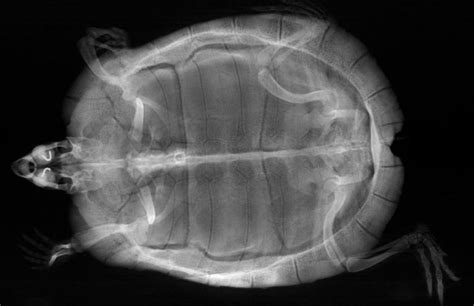

First up, let’s talk about the shell and the skeletal system . On a lateral turtle X-ray , the shell, comprising the carapace (top) and plastron (bottom), appears as a dense, bony outline. The vet will be looking closely at its integrity , checking for any signs of fractures, hairline cracks, or bone lesions that might not be visible externally. Sometimes, a trauma that seemed minor on the outside could have caused significant internal shell damage, and the side view X-ray is crucial for assessing this. They’ll also be evaluating the bone density of the shell and other skeletal structures, like the spine and limb bones. Reduced bone density, often appearing as thinner or less opaque bones on the X-ray, can be a tell-tale sign of Metabolic Bone Disease (MBD) , a common and serious condition in turtles caused by imbalances in calcium, phosphorus, and vitamin D3. MBD can manifest as generalized bone demineralization, pathological fractures, or abnormal bone growth. The lateral view allows for a clear assessment of the vertebral column, running along the length of the turtle’s body, checking for alignment, compression fractures, or any abnormal growths. The limb bones – humerus, radius, ulna, femur, tibia, fibula – are also visible, and the vet will be looking for fractures, dislocations, or other signs of injury or disease. Since turtles can be surprisingly resilient, they might not always show obvious signs of pain, making the X-ray an essential tool for uncovering these hidden skeletal problems. The clarity offered by the side view helps differentiate bone abnormalities from overlying soft tissues, ensuring an accurate diagnosis of skeletal health. The bony architecture of the shell, in particular, can reveal growth plate issues in younger turtles or degenerative changes in older ones, providing a comprehensive assessment of the animal’s osteological status.

Now, moving deeper, the lateral turtle X-ray provides an incredible window into the soft tissue structures and internal organs . This is where the side view really shines, allowing for the assessment of organs that would be heavily superimposed in a top-down image. One of the most important areas is the lungs . In a lateral X-ray , the lungs appear as relatively clear, air-filled spaces located dorsally (towards the back) within the shell. The vet will be meticulously examining these lung fields for any abnormal densities, fluid accumulation (which would show up as hazy or opaque areas), or granulomas (small, dense masses). These findings are classic indicators of respiratory infections like pneumonia, which are common in turtles, especially those kept in improper environmental conditions. The side view helps distinguish lung pathology from other dense structures, such as the shell or overlying limbs, giving a much clearer picture of the severity and distribution of the infection. A healthy lung should appear clear and well-inflated, and any deviation from this normal appearance is a cause for concern.

Next, the digestive system. The gastrointestinal (GI) tract , including the stomach and intestines, can be visualized. On a lateral X-ray , the vet looks for signs of impaction – foreign bodies like substrate, rocks, or other indigestible items that can get stuck. These show up as dense, sometimes oddly shaped, objects within the gut lumen. They also assess for gas distension within the intestines, which can indicate poor gut motility or blockages. The bladder is another key structure. If your turtle has bladder stones (uroliths) , these will appear as dense, often round or oval, radio-opaque structures within the bladder, which is located ventrally (towards the belly) within the pelvic canal. The lateral view is excellent for confirming their presence and estimating their size and number. For female turtles, the reproductive organs are a crucial focus. If a female is gravid (carrying eggs), the side view X-ray will clearly show the eggs within the oviducts, allowing the vet to count them, assess their size, and check for any signs of egg binding (dystocia), where eggs are unable to be laid. This is vital information for managing potential reproductive complications. Other structures, like the liver and kidneys , can sometimes be indirectly assessed for changes in size or density, though specialized imaging might be needed for definitive diagnoses for these organs. The overall soft tissue architecture, including fat pads and muscle density, can also give clues about the turtle’s general body condition and nutritional status. The remarkable detail provided by the lateral turtle X-ray ensures that your vet has the most comprehensive visual information to make an accurate diagnosis and develop an effective treatment plan, making it an indispensable tool for maintaining your turtle’s health and well-being.